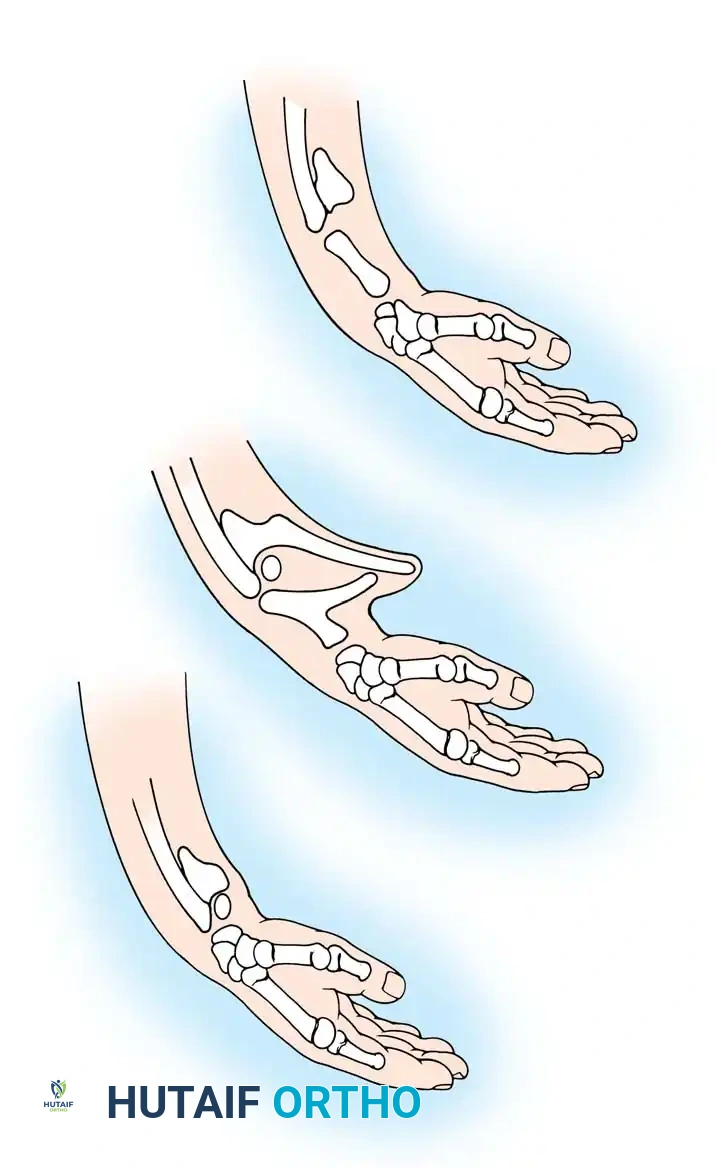

Growth and differentiation proceed in a strict proximal-to-distal fashion, governed by three primary signaling centers that dictate the three-dimensional spatial orientation of the limb:

- The Apical Ectodermal Ridge (AER): Located at the distal tip of the limb bud, the AER is responsible for proximal-to-distal growth. It secretes Fibroblast Growth Factors (FGFs) that maintain the underlying mesoderm in a highly proliferative state known as the progress zone.

- The Zone of Polarizing Activity (ZPA): Situated in the posterior (postaxial) margin of the limb bud mesoderm, the ZPA controls radioulnar (anterior-posterior) differentiation. The primary morphogen secreted by the ZPA is the Sonic Hedgehog (SHH) protein. Disruptions in SHH signaling explain the clinical phenomenon where ulnar-deficient limbs frequently present with associated preaxial (radial) hand deficiencies.

- The Wingless-Type (WNT) Signaling Center: Located within the dorsal ectoderm, this center secretes WNT-7a, which induces the expression of LMX1B in the underlying mesoderm, thereby determining the dorsal differentiation of the limb.

Fig. 76-1 Limb bud. The apical ectodermal ridge extends from anterior to posterior along the dorsal/ventral boundary of the growing limb bud. Proximal to the AER is the progress zone. Within the posterior mesoderm is the zone of polarizing activity. These centers are highly interconnected; limb patterning and growth depend entirely on their coordinated function.

By day 31 of gestation, the hand paddle becomes morphologically distinct. Through a genetically programmed process of cellular apoptosis (programmed cell death), the fissuring of the hand paddle is completed by day 36. The central rays form first, followed rapidly by the preaxial and postaxial digits. The formation of chondral elements, endochondral ossification, and the subsequent development of joints, musculature, and vascular networks follow in rapid succession. The entire embryological formation of the upper extremity is completed by the end of the 8th week of gestation.